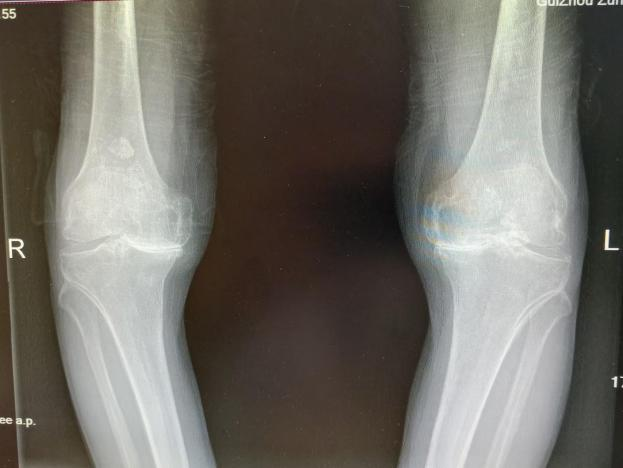

2025年11月1日,由遵义市医学会手外科分会主办、遵义市第二城市医疗集团(贵州航天医院)承办的遵义市医学会手外科分会学术交流会暨贵州省继续医学教育项目《急诊手外伤治疗临床研究新进展专题研讨班》在贵州航天医院成功举办,汇聚了遵义市手外科领域专家及基层医疗骨干,通过专题研讨与临床经验分享,共探急诊手外伤诊疗新进展。 会议特邀遵义市医学会手外科分会主任委员金文虎教授,遵义市医学会手外科分会副主任委员张子阳教授,遵义市医学会手外科分会常务委员杨绍浦教授,贵州航天医院陈明勇教授、赵兴东教授等遵义市手外伤专家进行交流分享;贵州航天医院党委委员、副院长彭亮参加会议并致辞,贵州航天医院骨科医务人员,遵义市第二城市医疗集团成员单位及红花岗区、绥阳县、桐梓县等区县医疗机构手外伤骨干参与。 贵州航天医院党委委员、副院长彭亮致辞 学术交流 本次学术交流以“急诊手外伤治疗临床研究新进展”为主题,通过理论授课与临床案例结合,共同探讨急诊手外伤临床诊疗全链条诊疗策略、关键技术、临床研究新进展,促进规范化诊疗技术向基层下沉,助力提升区域手外伤应急处置与修复能力。 贵州航天医院赵兴东教授分享《急诊手外伤的诊断与治疗原则》 贵州航天医院陈明勇教授分享《开放性骨折的治疗原则》 贵州航天医院张军教授分享《甲沟炎Winograd手术的临床应用》 贵州航天医院赵兴东教授分享《手部常见的皮肤缺损及治疗原则》 贵州航天医院张艳金教授分享《开放性骨折的清创术》 贵州航天医院冷家雄教授分享《下肢创面修复的常用皮瓣之股前外侧皮瓣》 贵州航天医院邬夏荣教授分享《踝关节慢性不稳的诊治》 贵州航天医院卢懿明教授分享《掌骨骨折》 贵州航天医院张艳金教授分享《手部肌腱的解剖与修复方法》 本次研讨班为遵义市手外科领域医务人员提供了深度交流契机,强化了医疗机构间的协作网络,进一步推动学科创新与临床实践融合,为健康遵义建设注入新动能。 贵州航天医院骨科专家简介 陈明勇 骨一科主任,副主任医师 临床擅长:从事创伤骨科工作约20年,对骨缺损、骨不连、骨肿瘤、肢体畸形等的肢体矫形重建及功能重建,慢性化脓性骨髓炎的根治治疗、糖尿病足的保肢治疗、快速康复理念(ERAS)下的老年骨折的诊治,四肢复杂骨折的诊治,四肢骨折等微创手术治疗具有丰富的临床经验。 2004年毕业于遵义医学院临床专业,曾在中国人民解放军总医院、广西医科大学第一附属医院、上海第六人民医院骨科进修。中国中西医结合学会骨伤科专业委员会横向骨搬移治疗糖尿病足及微血管网再生学组首届委员,遵义市医学会创伤分会常务委员。 瞿 晖 骨科党支部书记,骨二科主任,副主任医师 临床擅长:对骨科的常见病、关节外科、脊柱外科及运动医学疾病的诊治具有丰富的临床经验,熟练掌握骨科手术操作技术。 毕业于遵义医学院临床医学系,2005年前往广州中山大学第一附院骨显微医学部进修学习,2011年前往成都华西医院进修学习,并多次在省内外学习骨科相关知识,是中华医学会骨科分会会员。 赵小锋 中共党员,骨二科副主任,副主任医师 临床擅长:从事骨科临床工作11年,对骨科常见病、多发病诊疗有较为丰富的临床经验,擅长脊柱相关疾病诊断及治疗,尤其是颈、腰、腿疼痛疾病诊断及治疗,擅长胸腰椎骨折微创经皮穿刺内固定术、经皮穿刺椎体成形术、经皮穿刺脊柱内镜下腰椎间盘摘除术、单纯开创腰椎间盘摘除术、腰椎滑脱复位椎间植骨椎融合内固定术、腰椎管狭窄减压融合内固定术及人工髋、膝关节置换术等。 2012年毕业于遵义医学院外科学专业硕士研究生,2019年参加“遵义市115医学人才精英计划”于上海交通大学第一附属医院培训学习,2023年于北京大学第三人民医院脊柱外科进修学习,曾获得遵义市优秀医师荣誉称号。 遵义市手外科第一届委员,遵义市医学会创伤分会第一届委员,遵义市医学会创伤分会第二届委员,贵州省康复医学会第三届脊柱脊髓专业会委员,遵义市医学会烧伤与整形外科学分会委员,发表论文5篇,其中国家级核心期刊1篇,SCI论文1篇,主持市级课题1项并结题,参与市级课题2项。 赵兴东 骨科主任医师 临床擅长:擅长骨科的常见病及各种创伤、四肢骨折创伤修复、骨感染、手足疾病的诊治和手足体表畸形的矫形整复,熟练掌握骨科四肢骨病及创伤的手术操作技术,尤其在四肢关节复杂性损伤、手足外伤、组织缺损创面、难治创面的皮瓣修复方面及平足、高弓足矫形方面及四肢慢性疼痛诊治、康复方面具有丰富的临床经验。 硕士研究生,毕业于遵义医学院临床外科系,2015年前往山东省立医院手足外科进修学习;遵义市医学分会创伤分会第一、二届委员,遵义市手外科医学会第二委届员会常务委员;在省级及省级以上期刊发表文章9篇,参编著作2部,参与主持并完成市级课题1项,参与市级课题2项、省级课题1项。 张艳金 中共党员,骨科副主任医师 临床擅长:从事骨外科工作16年,对复合伤、多发伤的救治、四肢骨干骨折、关节周围骨折、骨肿瘤、骨髓炎等诊治具有丰富的临床经验。 中共党员,硕士研究生,2006年本科毕业于山西医科大学第二临床医学院,2011年研究生毕业于北京军区总医院;在“老年COPD患者合并髋部骨折的诊治”国际合作课题组研究两年,在老年髋部骨折的诊治方面具有丰富的经验,并发表论文6篇;主持遵义市级课题1项,承担遵义医科大学的临床教学工作,获得遵义医科大学优秀带教老师荣誉。编撰有《骨科疾病诊疗精粹》一书,开展2项新技术,编撰地方规范《务川自治县创伤骨科常见疾病诊疗规范》一书。 张俊凯 骨科副主任医师 临床擅长:从事骨科临床工作28年,对创伤骨折、骨感染、骨缺损、骨不连等外科诊治,四肢骨折的微创手术治疗,四肢复杂骨折(如关节内粉碎性骨折、多发骨折等)的损伤控制及手术治疗等具有丰富的临床经验。 1995年毕业于遵义医学院临床专业,2009年前往复旦大学附属医院骨科进修1年。 卢懿明 中共党员,骨科副主任医师 临床擅长:从事骨科工作18年,对创伤骨折、四肢骨折的微创手术治疗、四肢复杂骨折(如关节内粉碎性骨折、多发骨折等)的损伤控制及手术治疗,尤其是髋部骨折的PFNA等微创技术,踝关节骨折、膝关节周围骨折的Mipo微创技术等具有丰富的临床经验,开展了4项新技术,发明6项新型专利技术。 2005年毕业于遵义医学院临床专业,2017年,前往南方医科大学第三附属医院骨科进修半年,回院后运用Mipo技术对骨干骨折及干骺端骨折的治疗技术,同时积极开展骨盆骨折、髋臼骨折腹直肌外侧切口的应用;发表了多篇专业论文,经常参与省内外学术交流会授课,获得医院荣誉称号多个。 邬夏荣 骨科副主任医师 临床擅长:从事骨科工作16年,对四肢复杂骨折、骨肿瘤的诊治,尤其是足踝创伤、慢性踝关节损伤、平足症等诊疗具有丰富的临床经验。 2006年毕业于遵义医科大学临床医学专业,曾在陆军军医大学西南医院进修学习,发表多篇骨科学术论文。 余德怀 中共党员,骨科副主任医师 临床擅长:从事骨科工作10余年,对运动医学、骨关节、脊柱外科常见病、多发病的诊治具有丰富的临床经验。 硕士研究生,2011年毕业于遵义医学院临床医学专业,曾前往遵义医科大学附属医院运动医学专业进修学习;是贵州省医学会运动医学分会青年委员,西部关节镜联盟委员;发表多篇骨科学术论文。 冯 乾 骨科副主任医师 临床擅长:从事骨科工作近20年,熟练掌握骨科多发病及常见病的诊治,尤其对脊柱退变性疾病的诊断及治疗具有丰富的临床经验,主要研究脊柱微创相关治疗方式,能熟练开展椎间孔镜及UBE。 曾前往北京大学第三医院进修学习疼痛及椎间孔镜、首都医科大学友谊医院专业进修脊柱内镜;是贵州省康复医学会第三届脊柱脊髓专业委员会委员;发明专利3项、发表脊柱外科专业论文多篇。 贵州航天医院骨科简介 基本情况 贵州航天医院(原3417医院)骨科组建于1968年,前身是以创伤和断肢(断指)再植闻名于世的上海市第六人民医院骨科,中国断肢(断指)再植的奠基者、中科院院士陈仲伟等专家莅临科室指导医疗和教学,并在70年代开展了贵州省首例断肢(断指)再植手术。组建50余年来,诊治患者已逾百万,挽救了无数的伤病员,成为了保障遵义地区人民群众健康的重要支撑。 经过几代人的不懈努力,今天的骨科,已由创伤骨科发展至骨病、骨肿瘤、骨结核等领域,现有脊柱外科、关节外科、四肢创伤、手足外科四个亚专科,成为了集医疗、教学、科研于一体的综合学科,是贵州省临床重点专科、遵义市临床重点专科、遵义市骨科临床医学中心、遵义市基层骨科专科联盟理事长单位。 科室目前开放床位110张,共有医护人员50余人,副高级以上专家18人,硕士研究生15人。拥有一流骨科医疗设备多台,每年不定期选派优秀技术骨干到全国各大知名医学院校进修、学习、参观、交流,并邀请国内、国外知名专家教授来院进行交流、指导,通过不断引进国内外先进的诊疗技术,科室医疗技术水平稳步提升,为广大人民群众提供了优质的医疗服务。 专科特色 骨一科 (一)骨缺损、骨不连的肢体与功能重建 胫骨横向骨搬移技术治疗糖尿病足: (二)慢性骨髓炎的根治治疗 (三)肢体缺血性疾病如糖尿病足、脉管炎的保肢治疗 (四)皮瓣修复 (五)复杂创伤的治疗 (六)老年髋部骨折及小儿骨折快速手术 老年髋部骨折: 骨二科 (一)胸腰椎骨折微创经皮椎弓根螺钉固定术 (二)老年性骨质疏松性患者腰椎滑脱脊柱内固定术(骨水泥螺钉) (三)V形双通道脊柱内镜技术(VBE)腰椎融合术治疗腰椎退行性疾病 (四)老年性骨质疏松性骨折(PVP/PKP)术 (五)人工髋关节置换术 (六)双侧股骨头坏死人工全髋关节置换 (七)右侧全髋置换术后假体周围骨折翻修 (八)人工膝关节置换术 (九)人工膝关节假体松动翻修 (十)关节镜技术 传统手术切口 关节镜技术切口 诊疗范围 骨一科 1.四肢创伤、矫形。 2.手、足踝外科。 骨二科 End